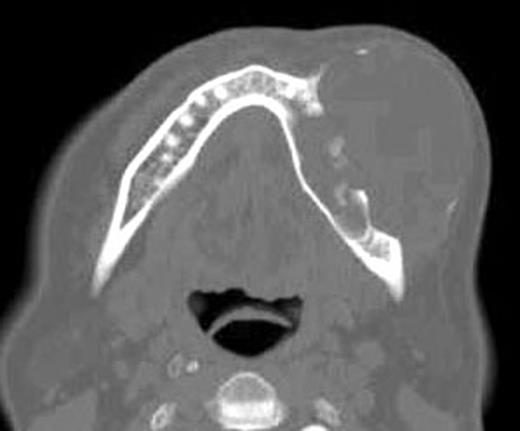

Three-dimensional images allowed for the visualization of the lesion in relation to relevant anatomical structures providing depiction of bone destruction in the body of the mandible. Preoperative 3D CT reconstruction indicated destruction of the buccal cortex of the mandible (left side) caused by the lesion and projection of osseous spiculae (Fig. 1A and B).

Frontal view of pre-operatory 3D CT images shows the destruction of bone and a spiculars osseous formation (a) and in lateral view show the destruction of the cortex (b).